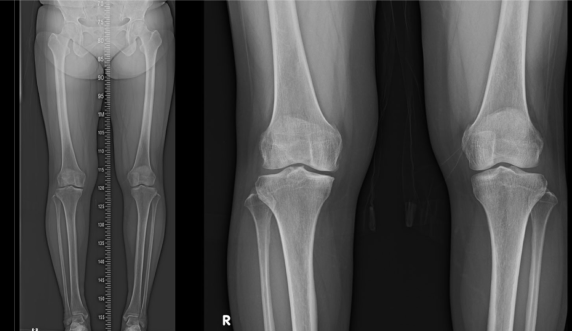

수술 전 환자의 상태